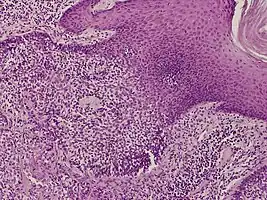

Histology

They are described as < 1 to 2 cm, pink/red shiny, exophytic lesions that can be pigmented and are clinically very similar to pyogenic granulomas.[3] Histologically, the cells as PAS-positive and clearly surrounded by normal keratinocytes. These tumors are surgically excised usually without complication or recurrence, although malignant porocarcinomas can recur and metastasize to local lymph nodes.[5]

Poroma eccrinale (hidroacanthoma simplex) Eccrine clear-cell poroma